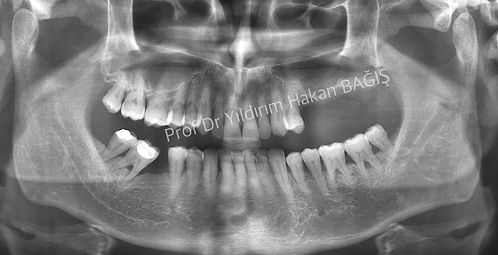

Üst çenede çiğneme alanlarında dişleriniz yok ve bu bölgede ağızda sabit kalan protezler istiyorsanız, tek çözümünüz implant uygulamalarıdır. Fakat, bazen üst çenedeki kemik istenilen kalınlıkta olmaya bilir. Bunun sebebi; adına, “maksiller sinus” denen kemiğin içindeki balon şeklindeki boşluktur. Sinüs Lifting veya sinüs yukarı alma bu balon şeklindeki boşluğun kemik benzeri bir madde ile doldurularak implant uygulamalarına hazır duruma getirilmesi işlemidir. Ne yazık ki, bu yöntem herkesin yapabileceği bir teknik değildir. Konusunda uzman kişilerin bile zorlanabileceği bir yöntemdir. Başarılı olmak ve üzerine diş yerleştirebilmek için günümüz şartlarında 6 ay beklenilmesi gerekir. Bazen operasyon başarısız olabilir ve maalesef hasta ve hekim yönünden olumsuzluklar olabilir. Mutlaka bu konular operasyon yapılmadan önce hastaya özenle anlatılmalıdır.